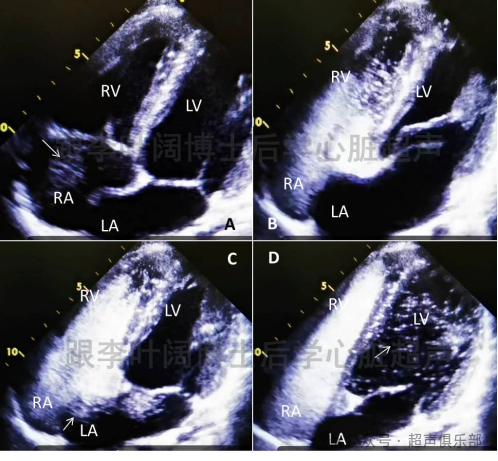

病例 患者男性,27岁,不明原因头痛,常规超声心动图未见明显异常,“发泡试验”PFO阳性。

图3 发泡试验超声心动图:A图为静息状态微泡初达右房;B图为激发初期,右心房、右心室微泡显著增强;C图为激发后,箭头所示为收缩期微泡瞬间自房间隔入左房;D图为舒张期,箭头所示左房微泡入左室,>30个/帧。